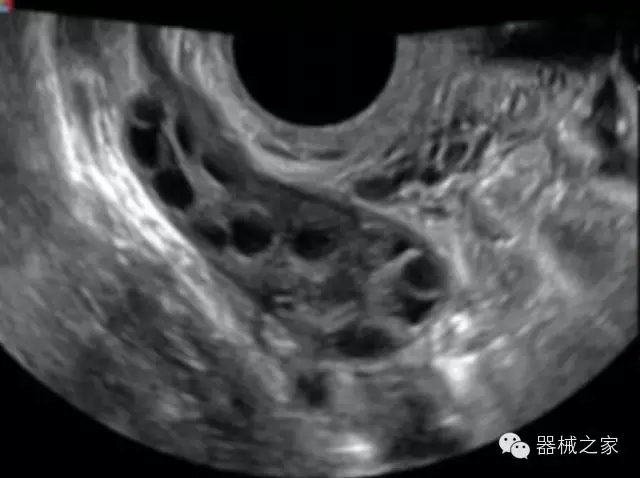

臨床圖片賞析

·亞陣元技術(shù):獨(dú)有的亞陣元技術(shù),對獨(dú)立晶片做二次切割,減少旁瓣偽像,增加臨床診斷的準(zhǔn)確性;

·μ-Scan微米成像技術(shù):開立獨(dú)有的μ-Scan技術(shù),還原出真實(shí)細(xì)膩、層次對比優(yōu)異的二維圖像;

·倒相諧波成像技術(shù):倒相諧波技術(shù)在去除基波信號的基礎(chǔ)上獲取兩倍二次諧波信號,提高組織圖像的對比分辨力;

·智能微血流成像技術(shù):智能微血流捕捉技術(shù)可以提取出隱藏在背景噪聲中的弱血流信號,大大提高低速血流的敏感性;

·實(shí)時(shí)的彈性成像技術(shù):提高了小器管(乳腺,甲狀腺、淺表軟組織腫瘤等)疾病鑒別診斷;

·高效3D/4D成像技術(shù):高速的4D幀頻,豐富的3D成像模式,智能斷層切片功能;

·獨(dú)有的大角度及實(shí)時(shí)溫控技術(shù),能同一切面顯示宮頸及宮體,有效減低了患者的痛苦,及保護(hù)粘膜保證了醫(yī)療安全;